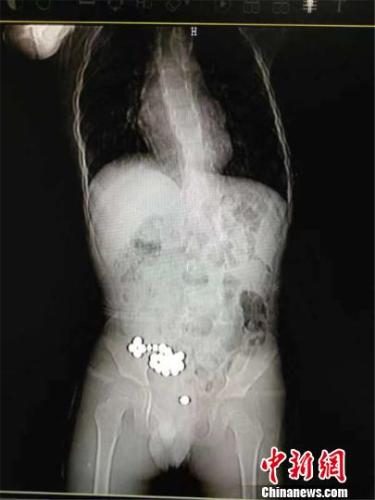

图为男童体内的磁力珠。医院供图

但3天过去了,磁力珠仍未排出,明明还不时地哭喊肚子痛,这下可把明明父母急坏了,赶紧带孩子去医院拍片。在X光片下,一排磁力珠清晰可见,细数竟有20颗之多,每颗珠子的直径约为0.5厘米。随后,父母连夜把明明送到了宁波市妇儿医院急诊科,经过一系列检查,明明被送入手术室。